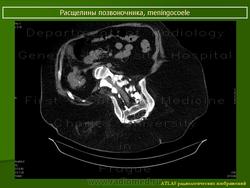

Видела люмбосакральную агенезию в 30 лет, кт обп+мт по поводу мкб. Могу кадров накидать.

Парень инвалид-колясочник, полностью сохранен в остальном и очень позитивен.

обещанное